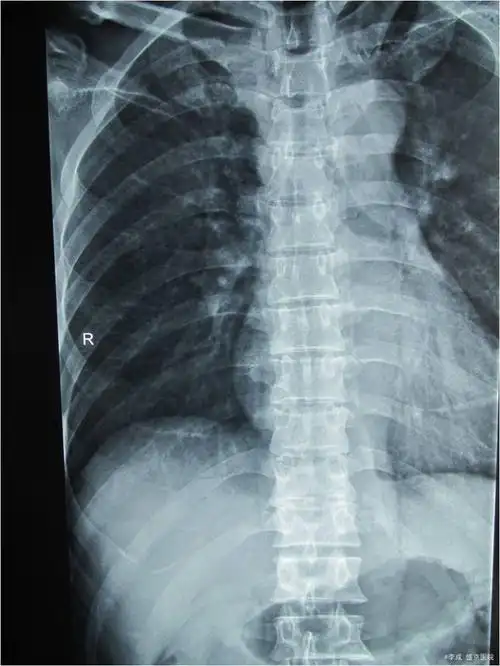

胸椎压缩性骨折